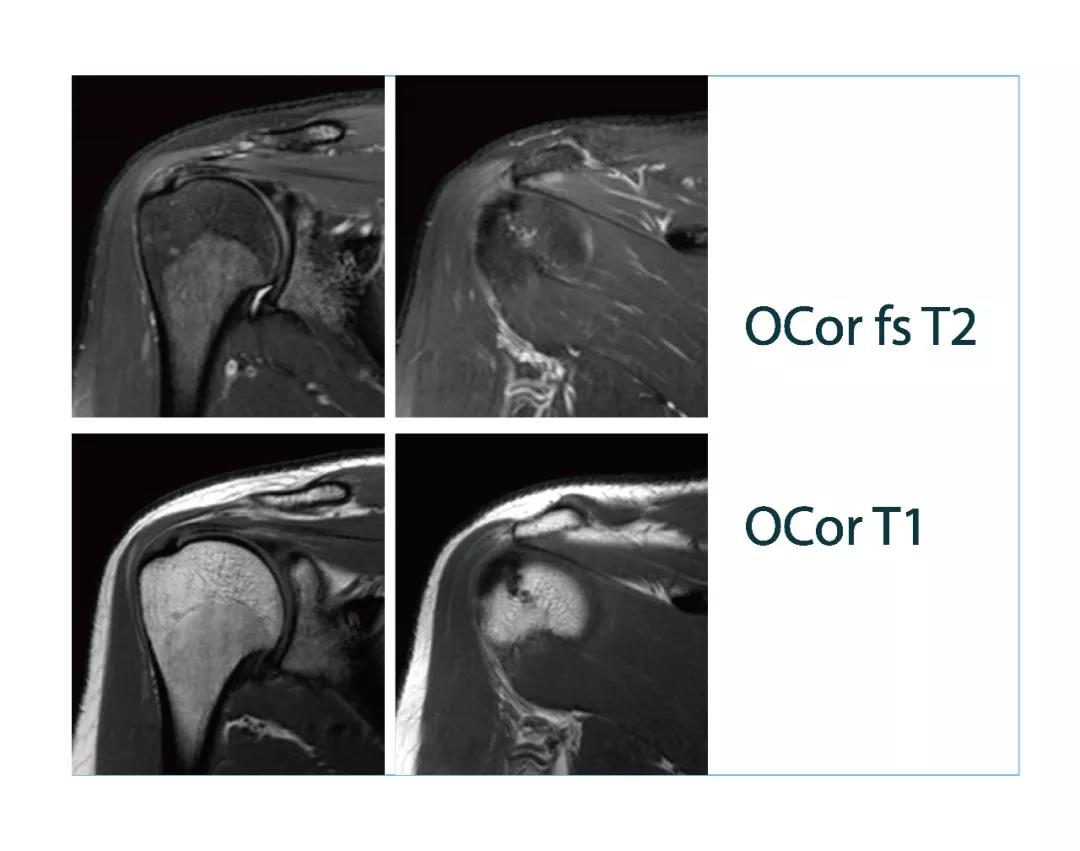

【朗润影像档案】20180323磁共振影像病例结果讨论

【朗润影像档案】磁共振影像病例分享(编号20180323)